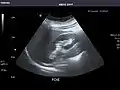

Left kidney

Kidneys: Right and left kidneys measure 11.5 cm and 12 cm in length respectively. No hydronephrosis. Small left lower pole kidney cyst.